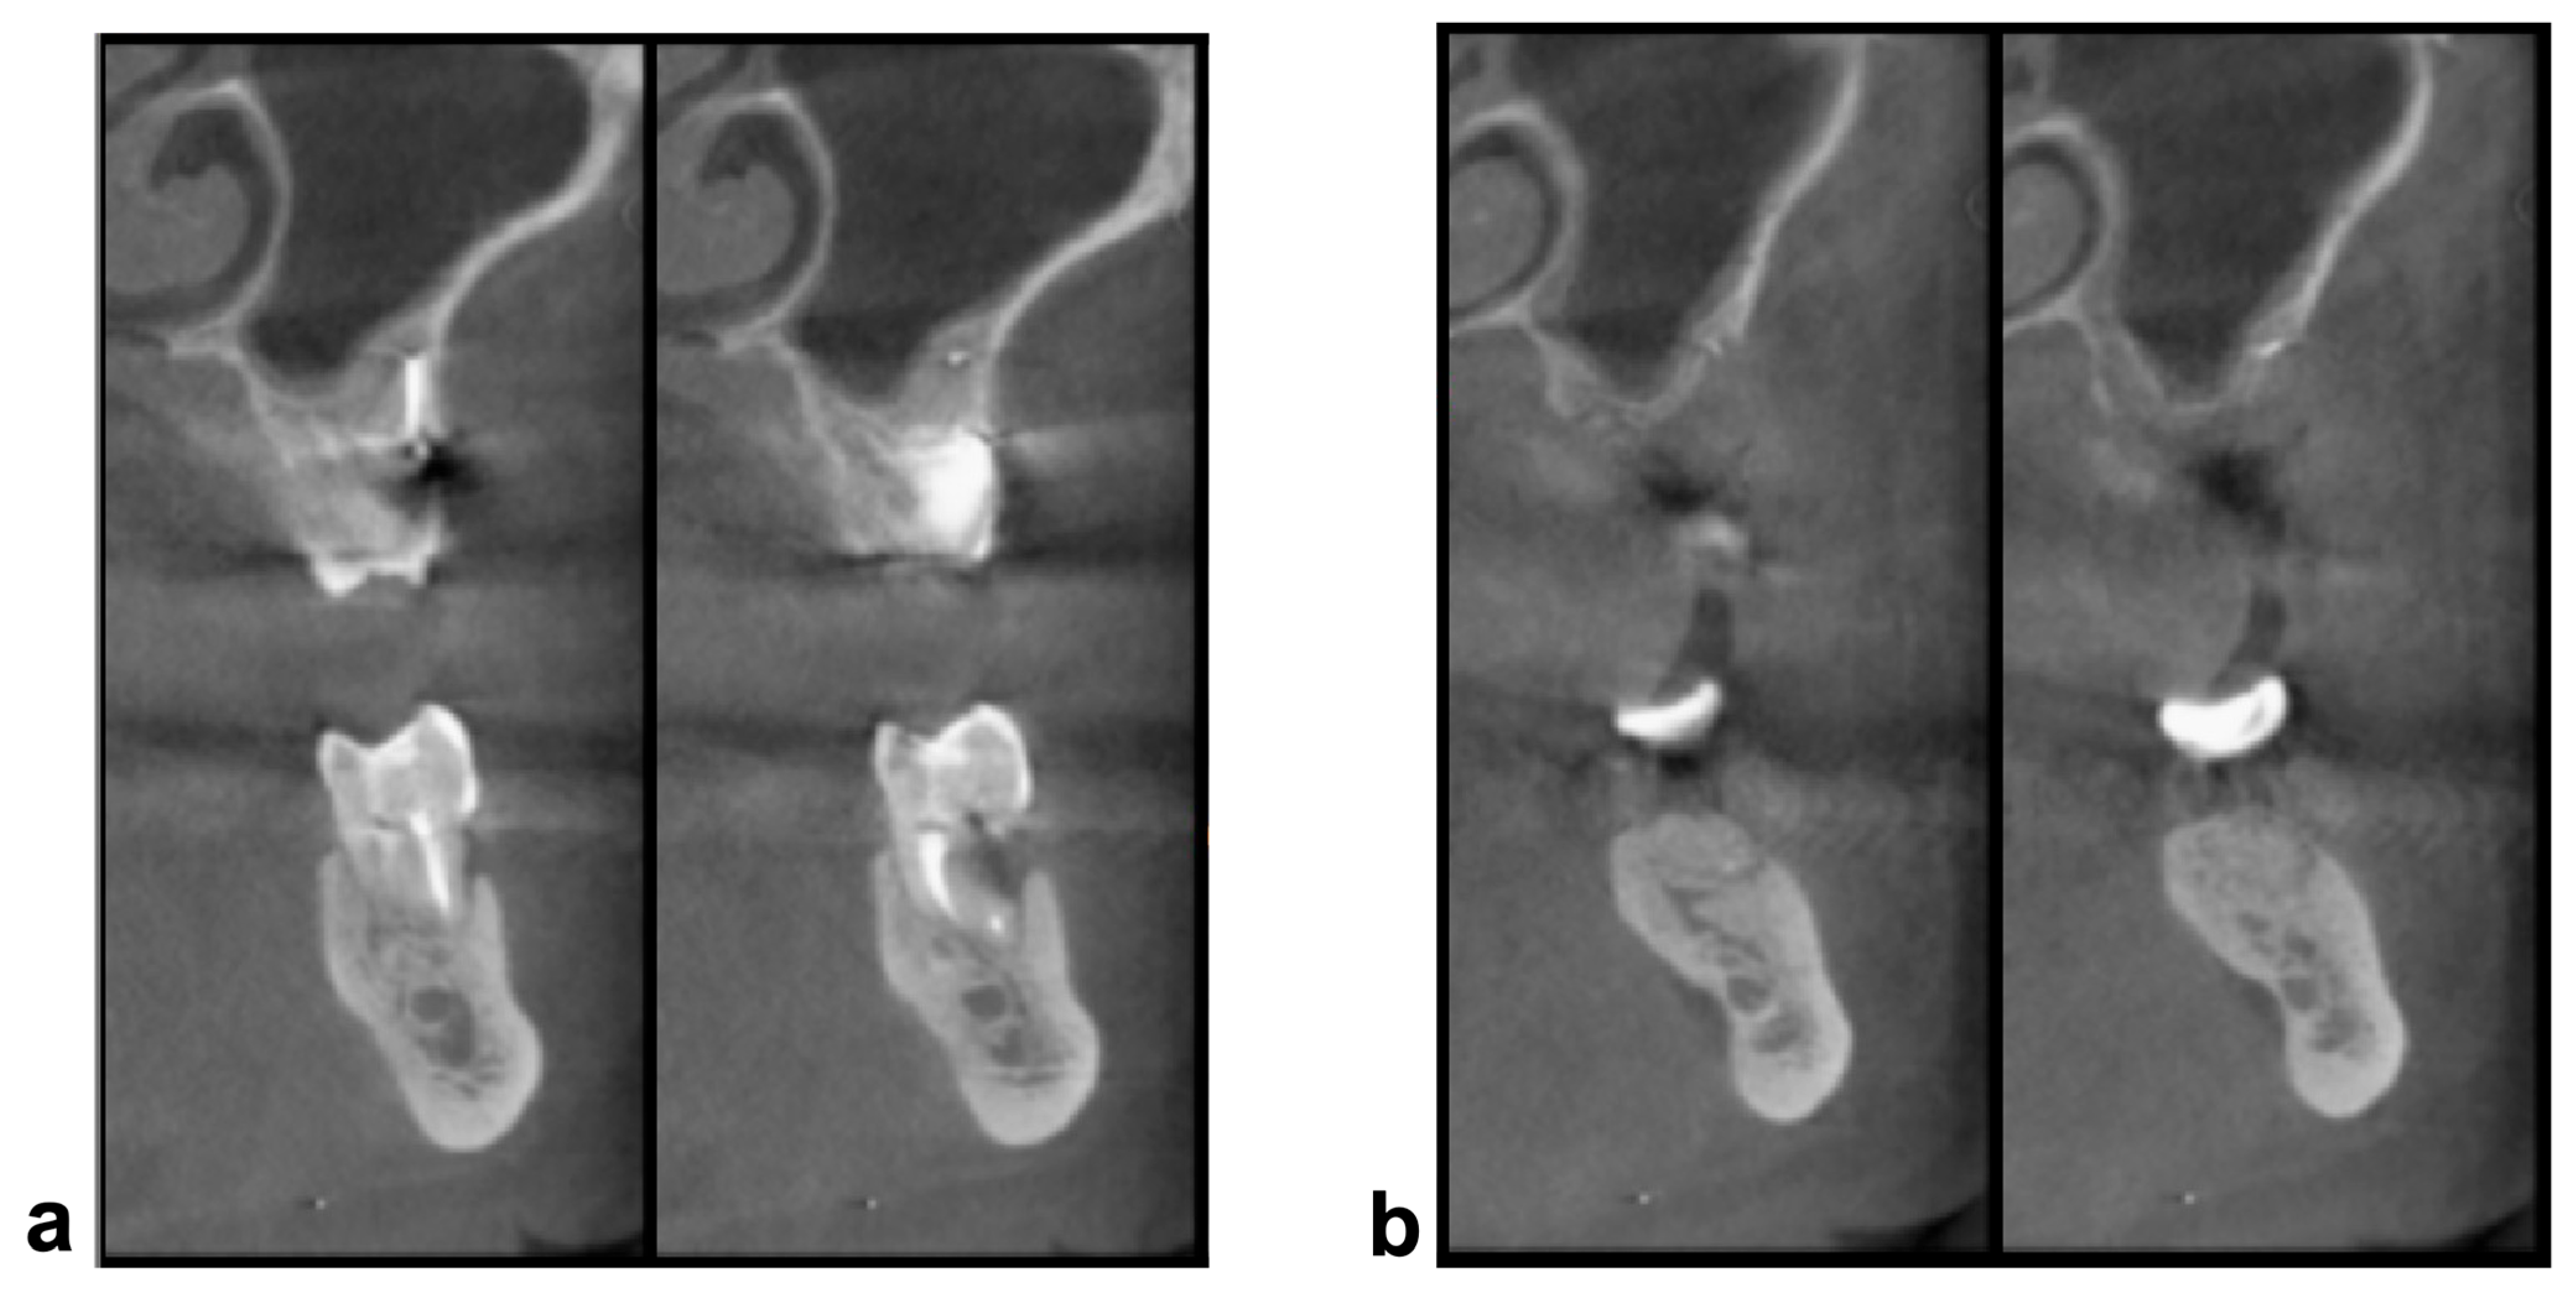

2. Materials and Methods

3. Results